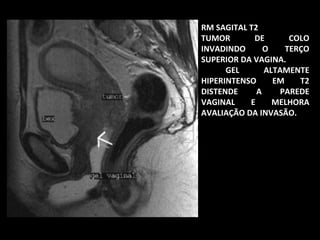

RM SAGITAL T2

TUMOR

DE

COLO

INVADINDO

O

TERÇO

SUPERIOR DA VAGINA.

GEL

ALTAMENTE

HIPERINTENSO

EM

T2

DISTENDE

A

PAREDE

VAGINAL

E

MELHORA

AVALIAÇÃO DA INVASÃO.